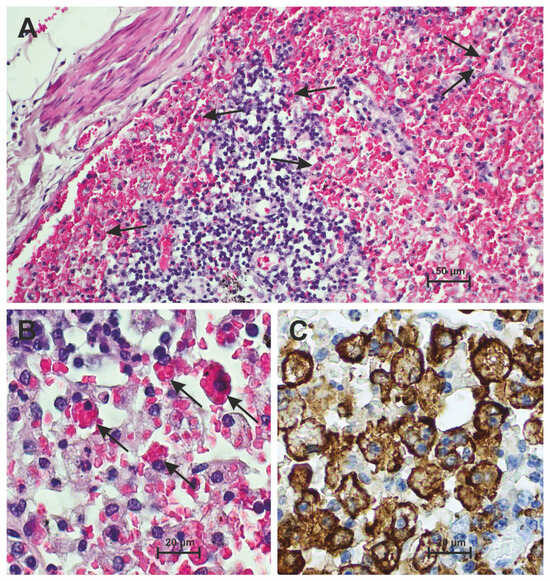

3.2. Hemophagocytosis Is Found in the Lymph Nodes of Patients Who Have Died from Severe COVID-19

3.3. Hemophagocytosis Is Found in the Bone Marrow of Patients Who Have Died from Severe COVID-19